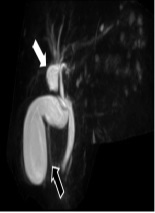

Intrahepatic Bile Duct Cyst Calculus and Gallbladder Stones Treated with Surgery: A Case Report

Koichi Kimura*, Yasuhiro Doi, Yasushi Takii, Ryosuke Tsutsumi, Kensuke Kudou, Norifumi Tsutsumi, Tetsuo Ikeda, Soichiro Maekawa